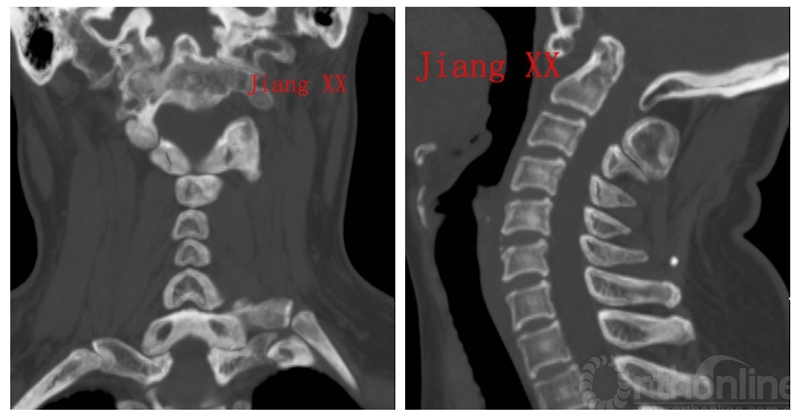

术前CT

术后一年CT